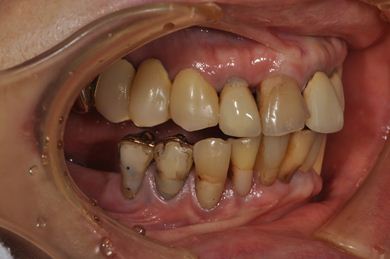

抜歯即日スピードインプラント治療+インプラント除去+セラミック治療

| 性別/年齢 | 女性 / 76歳 | ||||||||||||||||||||||||||||||||

| 主訴 | 20年前に入れたインプラントの周囲が腫れて気になっている。左下の一部治療後の歯が欠けている。 | ||||||||||||||||||||||||||||||||

| 治療内容 | インプラント5本(抜歯即日スピードインプラント)、ハイブリッドセラミック9本(セラミック用土台2本)、メタルボンドセラミック2本(メタルボンド用土台1本)、インプラント除去1本 | ||||||||||||||||||||||||||||||||